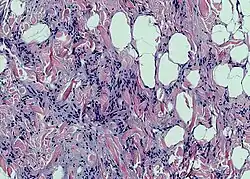

| Photomicrograph of a spindle cell lipoma. | |

According to histology, the lesion is made up of tiny, homogeneous spindle cells and mature adipocytes combined with eosinophilic collagen bundles inside a myxoidstroma. According to immunohistochemical staining, the spindle cells are positive for CD34 but negative for S-100 protein.[3]